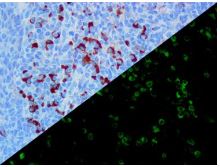

Bio SB has developed a highly sensitive Immunofluorescence and non-biotin monovalent Fab micropolymer IHC detection systems for the detection of IVD antibodies for Complement (C1q, C3c, C3d, C4c, C4d), Serum Proteins (Albumin and Fibrinogen) and Immunoglobulins (IgA, IgD, IgE, IgG, IgM, Kappa and Lambda) related to autoimmune conditions. Our innovative IF and IHC detection systems and high affinity antibodies, have opened the doors for a faster and accurate Immunofluorescence and Immunohistochemistry applicable to Autoimmune Disease like Nephropathies and Lupus.

These antibodies and detection systems are intended for use in Immunohistochemical (IHC) and Immunofluorescence (IF) applications of formalin-fixed paraffin-embedded tissues (FFPE), frozen tissue sections and cell preparations.

InDirect Immunofluorescence Antibodies

InDirect Immunofluorescence Detection

Rabbit FluoroDetector FITC |

Rabbit FluoroDetector FITC with FluoroMounter |

Rabbit FluoroDetector FITC with FluoroMounter with DAPI |